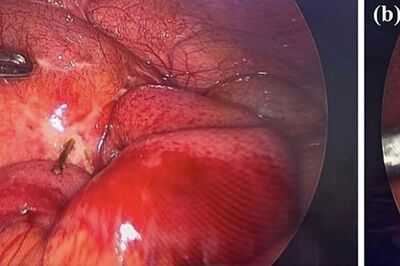

The medics then ordered an emergency laparoscopy to investigate further, and that's when they found the cause: a wooden toothpick, which had perforated the bowel, as reported by NeedToKnow.

Doctors were able to remove it from the bowel, and noted the area had already sealed over, leaving them to apply surgifoam [a sterile sponge used to control bleeding] to the extraction site.

The rest of the area was examined but thankfully the toothpick hadn’t caused any further damage.